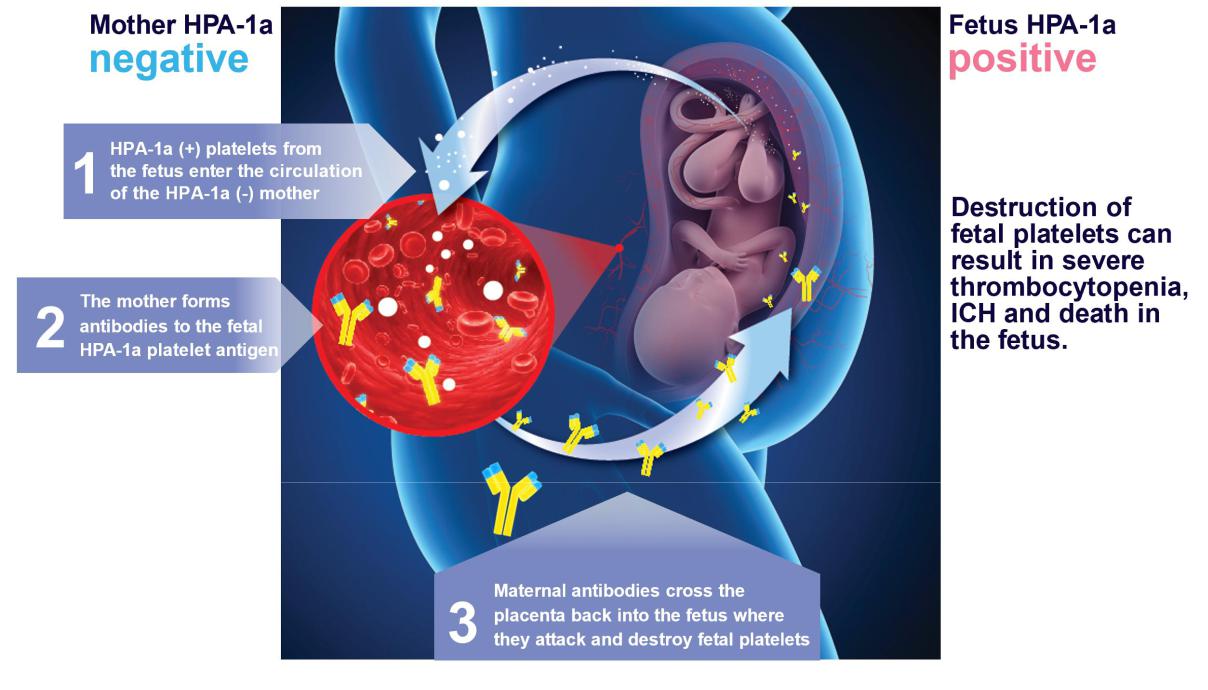

Like Rh disease, FNAIT is a disorder that occurs during pregnancy when an expectant mother’s immune system attacks a specific antigen on the blood cells of her fetus, leading to their destruction. This results in an increased risk of bleeding in the fetus and newborn. In the majority of cases, the effects of FNAIT are mild; however, up to 20% of FNAIT cases experience intracranial hemorrhage ("ICH"), which can lead to devastating outcomes such as miscarriage, stillbirth, loss of the newborn and severe lifelong neurological disabilities in those babies that survive.

FNAIT is caused by a mismatch in the type of HPA-1 that is expressed by the expectant mother and the fetus. There are two predominant forms of HPA-1, known as HPA-1a and HPA-1b, which are expressed on the surface of platelets. These two alleles differ by a single amino acid. Individuals who are homozygous for HPA-1b, meaning that they have two copies of the HPA-1b allele and no copies of the HPA-1a allele, are also known as HPA-1a negative. Upon exposure to HPA-1a, these individuals can develop antibodies to that antigen in a process known as alloimmunization. In expectant mothers, alloimmunization can occur upon mixing of fetal blood with maternal blood. When alloimmunization occurs in an expectant mother, the anti-HPA-1a antibodies that develop in the mother can cross the placenta and destroy platelets in the fetus.

Pathophysiology of FNAIT

There are no approved therapies to treat or prevent FNAIT and expectant mothers are not currently screened for FNAIT risk. Today, expectant mothers at risk of FNAIT are typically only identified following the delivery of an FNAIT affected child. These mothers may be treated during subsequent pregnancies with weekly administration of IVIG, along with the oral steroid immunosuppressant prednisone. While IVIG administration can potentially mitigate the detrimental effects of anti-HPA-1a antibodies, it does not prevent alloimmunization, is costly, time-intensive, difficult to tolerate and associated with significant treatment-related complications.

A mouse model of FNAIT has been created in which the amino acids comprising the HPA-1a antigen are reconstituted in the mouse gene. These transgenic mice (referred to as APLDQ mice based on the amino acid changes) recapitulate multiple aspects of FNAIT. Administration of anti-HPA-1a antibodies to APLDQ mice leads to destruction of APLDQ platelets and severe thrombocytopenia. Injection of platelets from APLDQ mice into wild-type mice can induce an HPA-1a specific immune response. Finally, wild-type female mice pre-immunized with APLDQ platelets, when bred with APLDQ male mice, give birth to severely thrombocytopenic pups, many of which exhibit an accompanying bleeding phenotype. Treatment of these pregnant female mice with IVIG resulted in lowering the level of anti-APLDQ antibodies in the fetus and a reduction in thrombocytopenia.